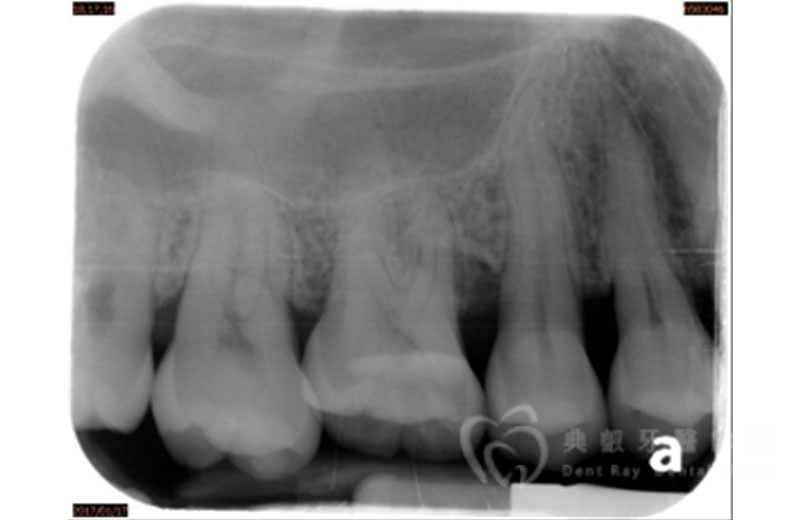

牙周手術案例三

術後六個月